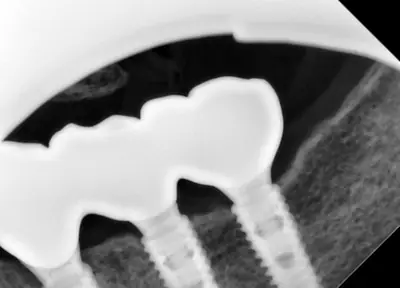

치과 치료를 두려워하는 분들에게 희망적인 사례를 소개합니다. 부산에 거주하던 60대 여성 환자가 치과 공포로 치료를 미루다 치아 상태가 악화되어, 의식하 진정요법을 통해 안전하게 임플란트 치료를 받은 이야기입니다. 환자는 병원 트라우마와 주사 공포, 치과 공포증이 있었지만, 전문의의 세심한 관리와 진정요법 덕분에 큰 불안 없이 치료를 마칠 수 있었어요. 치료 과정은 발치, 임플란트 수술, 인상 채득, 보철물 장착까지 단계별로 진행되었으며, 치료 후 자연스럽고 안정된 치아와 잇몸 라인을 확인할 수 있었습니다. 이 사례는 치과 공포증이 심한 분들도 적절한 진정요법과 신뢰를 바탕으로 치료받을 수 있음을 보여줍니다. 먼 거리에서도 찾아오는 환자들이 많은 이유는 바로 이런 진심 어린 진료와 결과 덕분이죠. 치과 치료에 대한 두려움이 있다면, 전문가와 상담하여 적합한 방법을 찾는 것이 중요합니다.